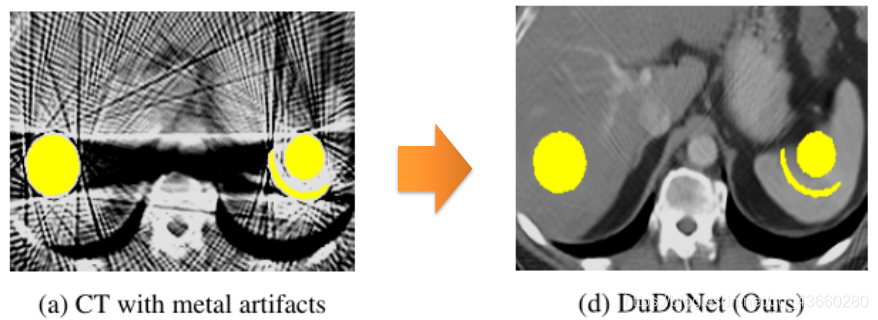

金属伪影示意图

黄色为金属,条纹为金属伪影,使图像质量严重下降,影响诊断结果的判别

黄色为金属,条纹为金属伪影,使图像质量严重下降,影响诊断结果的判别

宏观效果如下:有效的减少金属伪影并恢复细节